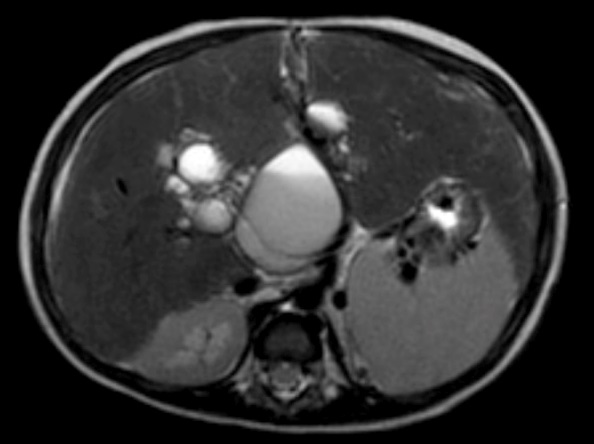

A vascular doppler sonography disclosed multiple cysts in right liver lobe, splenomegaly and widened caliber of portal venous which indicate portal hypertension. An abdominal CT scan with contrast was also conducted. Hepatomegaly, dilatation of intrahepatic biliary duct particularly at the right lobe, the largest cyst measured 5,47 x 5,77 x 5,54 cm, suggested Choledochal cyst type V (Caroli’s disease, according to Todani’s classification), cholangitis and cholecystitis were found (Figure 3). There were also splenomegaly and right nephrolithiasis.

Figure 3: Abdominal CT scan.

Abdominal CT scan with contrast: dilatation of intrahepatic biliary duct particularly at the right lobe, the largest cyst measured 5,47 x 5,77 x 5,54 cm, suggested Choledochal cyst type V, Cholangitis, Cholecystitis, splenomegaly, nephrolithiasis.